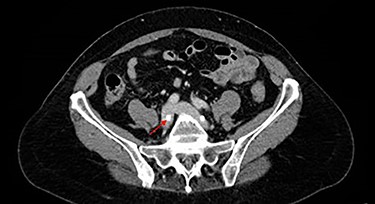

A 62-year-old female presented with low back pain. She had a prior history of a work-related injury that led to lumbar spinal fusion of L4–L5 at an outside hospital. She had some improvement in symptoms following the revision surgery, but continued to experience back pain and sought neurosurgical evaluation in our clinic. Physical exam was notable for 5/5 strength in the lower extremities bilaterally with normal patellar and Achilles reflexes. CT of the lumbar spine was concerning for the right L5 screw abutting the vasculature, so a CT angiogram and CT venogram of the abdomen were obtained (Fig. 1).

CTV showing right L5 screw (red arrow) indenting right common iliac vein.

The venogram demonstrated that the tip of the right L4 screw slightly indented the IVC and the right L5 screw moderately indented the right common iliac vein. After discussing the results with the patient, a plan was made to undergo surgery for removal of hardware, with vascular surgery present in case bleeding from venous injury was encountered after hardware removal.